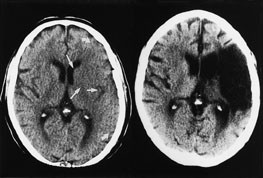

De følgende eksempler er hentet fra pasienter innlagt i Nevrologisk avdeling, Haukeland Sykehus, med akutt cerebral iskemi og undersøkt med CT innen tre timer og ti minutter etter symptomdebut (bildet til venstre, fig 1 – 4) og med oppfølgende CT (bildet til høyre, fig 1 – 4). Bildene illustrerer de forannevnte kardinaltegn (tab 1).

Omfattende mediaskade i mer enn en tredel av a. cerebri medias forsyningsområde (fig 4). Hypodenst vev ved CT betyr irreversibel skade. Hypodensitet oppstår som følge av cytotoksisk ødem. Ødemet fører gradvis til utplanert relieff på hjerneoverflaten og i insularegionen. Et indirekte tegn kan være redusert volum av fissura Sylvii og/eller mindre ventrikkelstørrelse på den aktuelle siden.